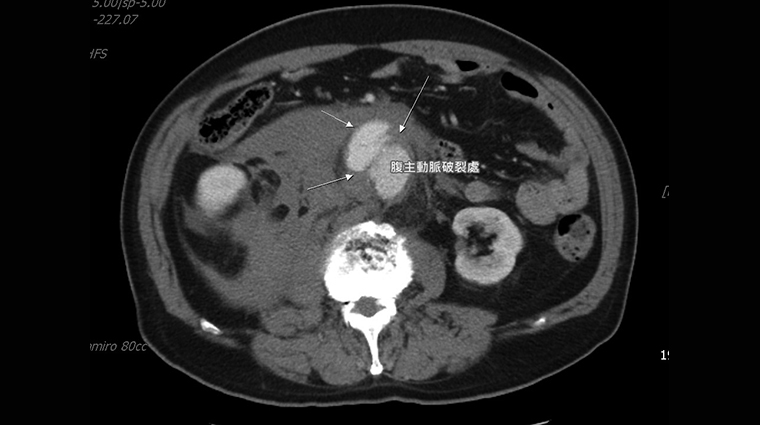

▲突然的腹部劇烈疼痛原因可能來自腹部主動脈瘤破裂,須盡速就醫。(圖/羅東博愛醫院提供)

【NOW健康 傅婷/宜蘭報導】宜蘭1位67歲李先生因突發腹部劇烈疼痛至羅東博愛醫院急診就醫,經電腦斷層掃描發現腹部有顆8.2公分的腹主動脈瘤破裂,隨時有出血致死的危險,就像體內有1顆不定時炸彈爆炸,所幸在進行緊急手術治療後,搶救回寶貴性命。